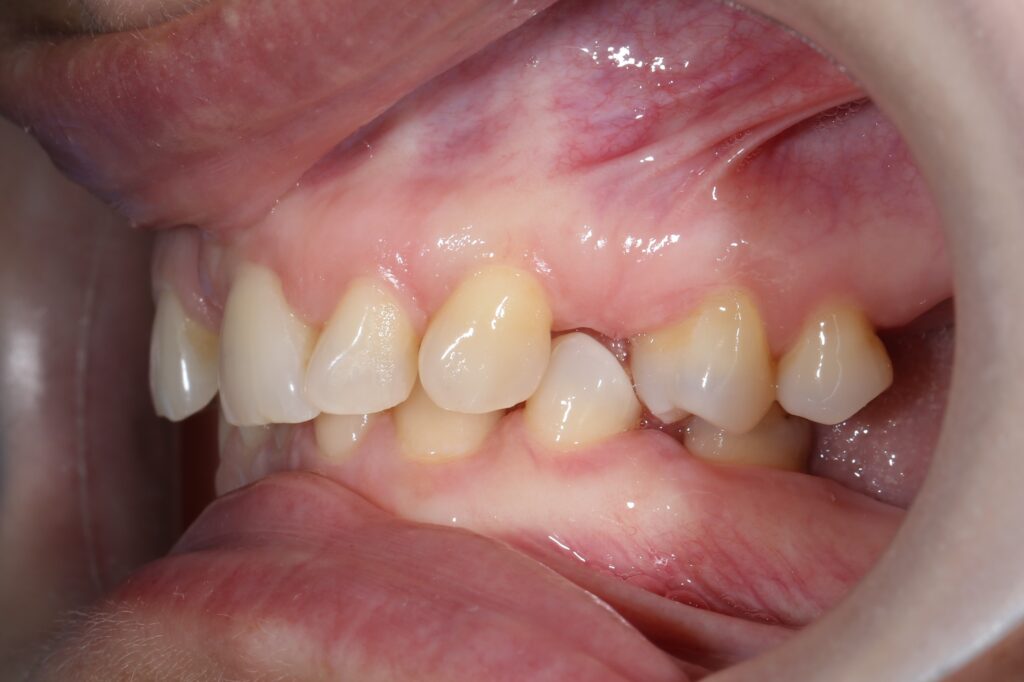

Результаты ортодонтической части

Была установлена брекет-система Damon Q. Срок лечения брекетами составил 11 месяцев.